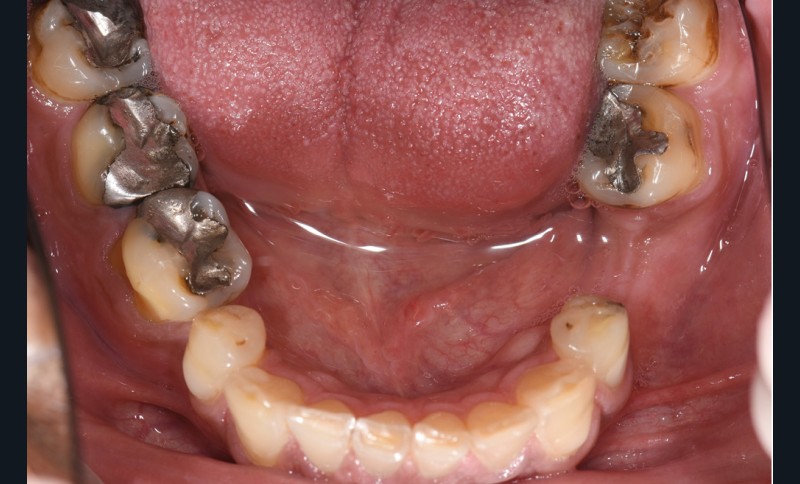

L’usure dentaire est de plus en plus fréquente au sein de nos cabinets. Nos patients y sont sujets de par leur alimentation parfois plus acide, leur mode de vie souvent plus stressant, et également une hygiène qui s’améliore et des dents qui vieillissent davantage.

L’étiologie de cette usure est multifactorielle, revêtant une composante de type attrition (usure par contact dento-

dentaire), une composante abrasive avec un brossage traumatique et, en dernier lieu, une légère composante tribo-érosive de par une pratique importante de sport avec gel et boisson acide (fig. 1-4) [1].